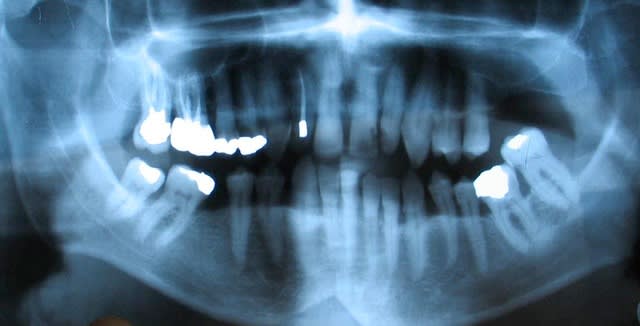

L'occlusion est a chier, avec endomaxillie, déviation des milieux, inversé d'articulé à gauche, mais pas de trouble ATM

Le contrôle de plaque est pas terrible, il y a une parodontite chronique ( amibe, bâtonnet ++ , PN ++ ). Le plan de ttt est d'extraire 37, de traiter la parodontite, de couronner ce qu'il faut, mais quand est-il de sa demande initial ?